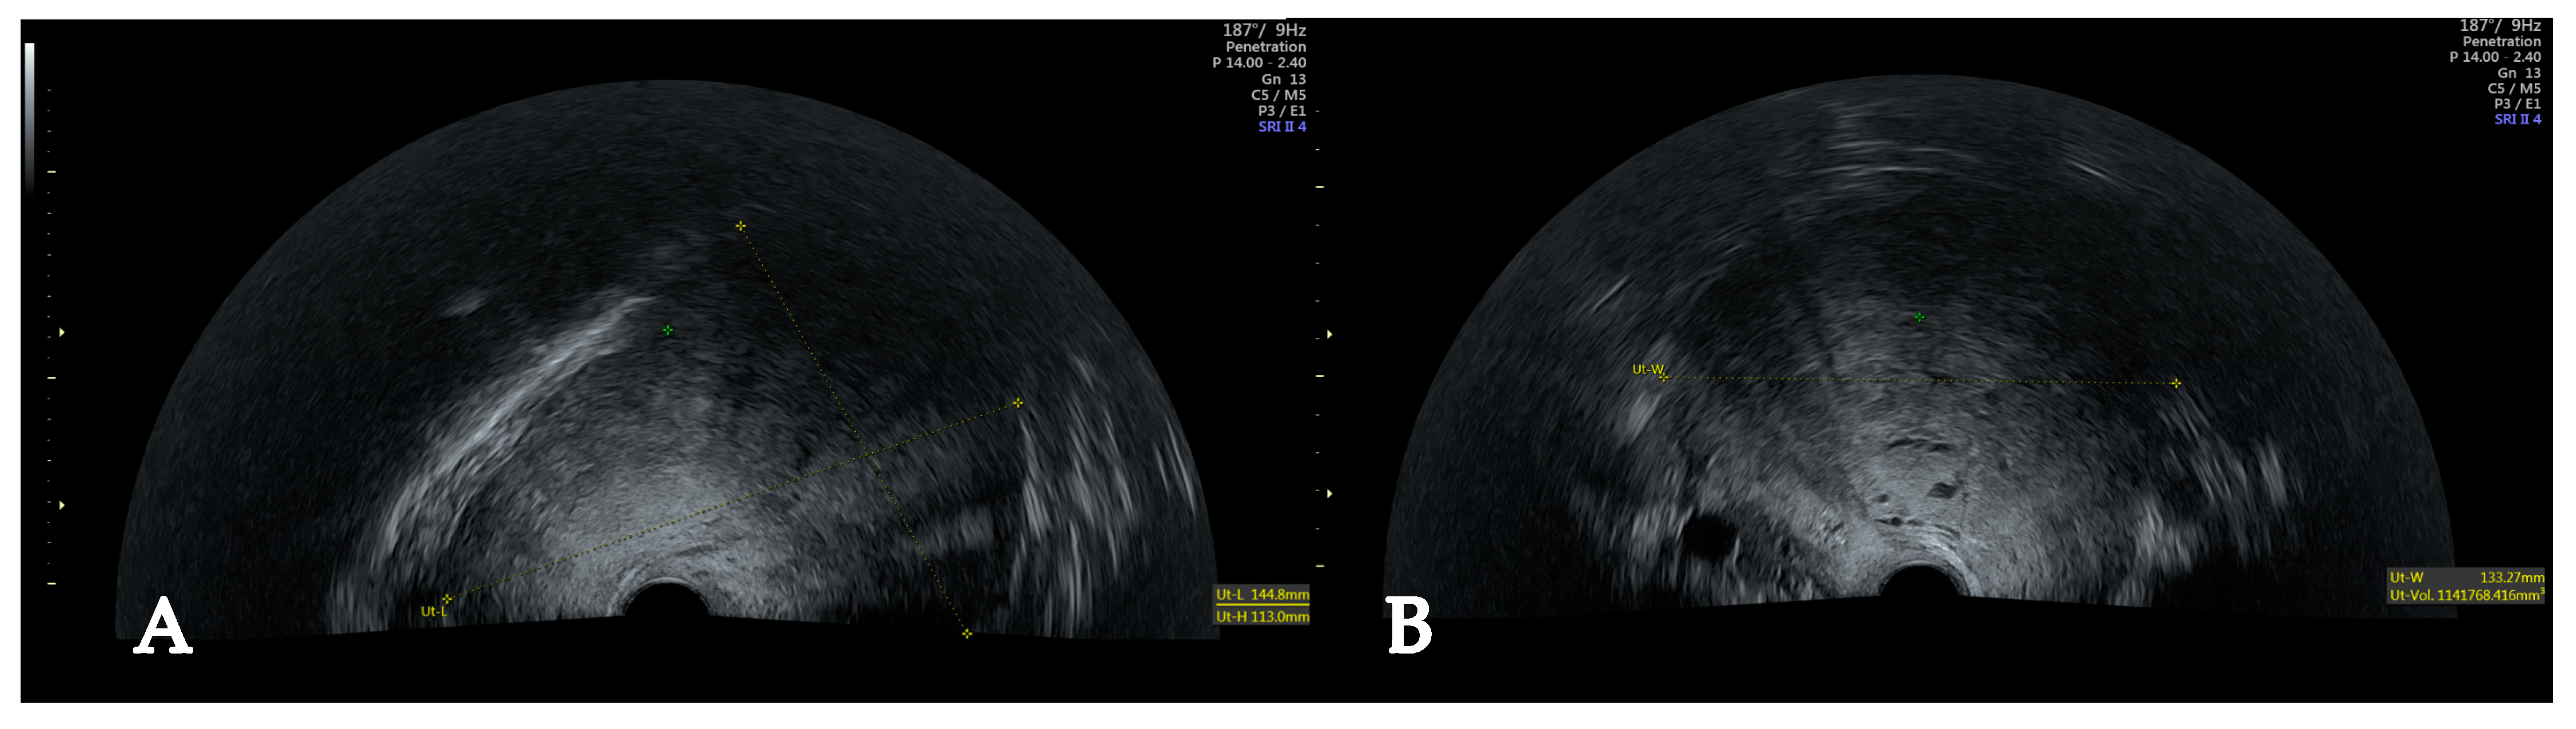

2. Case

4.1. Diagnostic Challenges